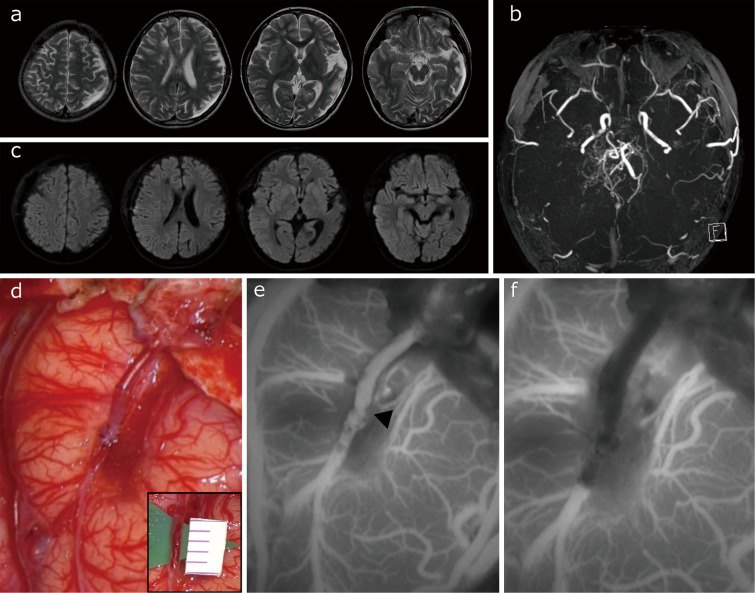

Pediatric patients with moyamoya disease frequently show rapid progression with a high risk of stroke. Indirect revascularization is widely accepted as a surgical treatment for pediatric moyamoya disease, but it does not augment cerebral blood flow immediately, which leaves patients at risk for stroke peri-operatively. This delay in flow augmentation may make adding direct bypass the better option. This study documents our cases of direct bypass failure that underwent indirect bypass supplemented with superficial temporal artery-middle cerebral artery bypass to evaluate the adverse effects of direct bypass failure. A retrospective review of all surgeries for pediatric moyamoya disease after introducing intraoperative indocyanine green videoangiography to confirm direct bypass patency identified 78 surgical hemispheres. Direct bypass failure was defined as failure to confirm blood flow from the superficial temporal artery to the middle cerebral artery on indocyanine green videoangiography. The occurrence of ischemic complications was evaluated by magnetic resonance imaging. During the period, postoperative ischemic complications were seen in 3 surgical hemispheres (3.8%) and one contralateral hemisphere (1.3%). One case in which hyperventilation was difficult to control postoperatively developed extensive cerebral infarction. Direct bypass failure was seen in 3 patients (3.8%), none of whom had additional cerebral infarction on magnetic resonance imaging. The results of this study indicate that failure of direct bypass surgery does not necessarily lead to cerebral infarction. Based on these results, surgeons can safely attempt to add a direct bypass to an indirect bypass, with special attention to perioperative patient management.

Abstract Image